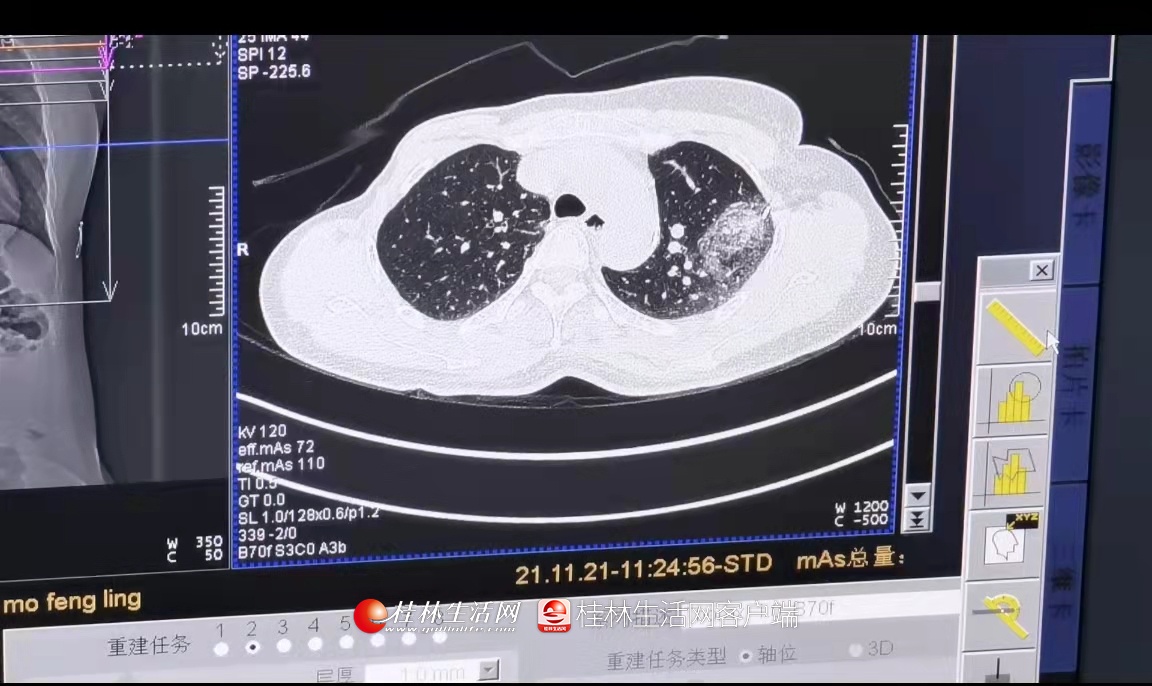

近日,广西壮族自治区南溪山医院呼吸与危重症医学科一区联合医学影像科顺利完成了两例在CT引导下进行的双肺结节微波消融术。

此次手术的两位患者莫女士和凌女士均为肺内两个IV类上肺结节病例。莫女士在1年前已经发现肺内结节,但未能进行积极治疗,内心十分忧虑;而凌女士2年前罹患左侧乳腺癌,此次复查发现左肺新发两个磨玻璃样结节,伴血管穿行,高度怀疑转移瘤。正在两人为自己的病情一筹莫展之时,得知南溪山医院能够开展CT引导下的肺结节微波消融术,不约而同到该院呼吸一病区就诊,经肺部CT检查发现两人均有双个肺结节病变,经呼吸一病区主任佘巍巍博士详细诊治,他认为肺内IV类磨玻璃结节恶性度高,若肺内出现两个IV类结节,则风险更高,考虑两位患者一般情况较差,且患者及家属担心外科手术风险及不能耐受手术,于是决定为她们采用CT引导下肺结节双针微波介入消融的手术方式,术后两位患者情况良好。消融后的实时影像结果显示病灶完全被覆盖,治疗效果立竿见影,莫女士和凌女士开心地向佘博士团队竖起了大拇指,感谢他们解决了自己的心头大患。